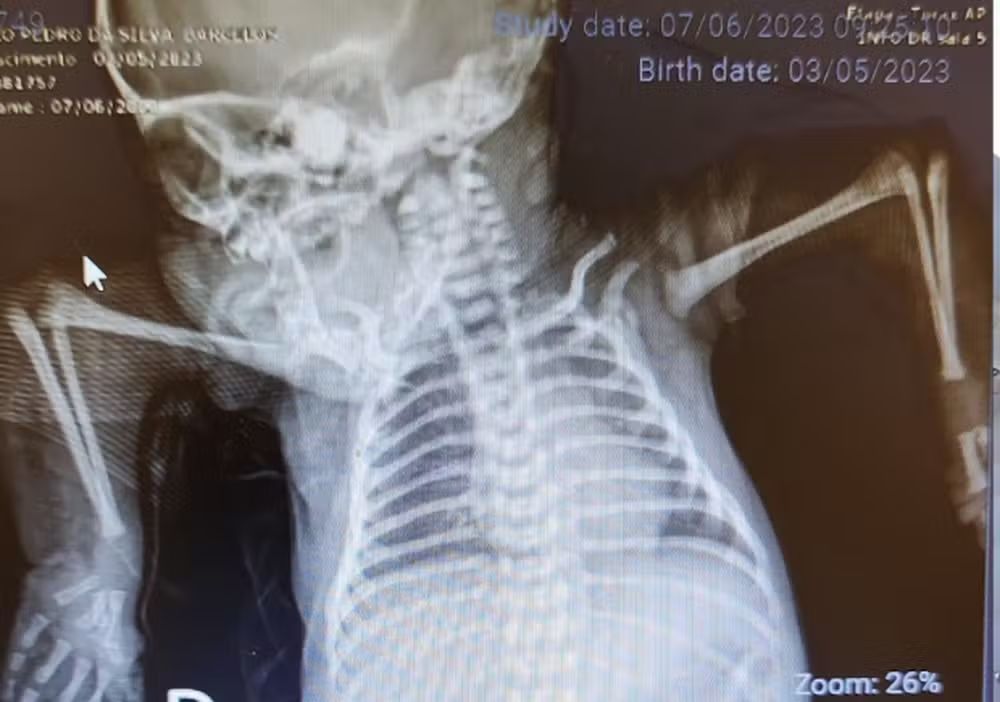

Para o pequeno João Pedro, de apenas um ano e nove meses, levar a mamadeira até a boca com as próprias mãos é uma conquista. Diagnosticado com artrogripose múltipla congênita, - uma condição rara que afeta articulações e músculos -, ele nasceu sem conseguir movimentar braços, dedos, punhos e cotovelos. Graças ao tratamento realizado no Instituto Nacional de Traumatologia e Ortopedia (INTO), João Pedro vem recuperando sua autonomia e já consegue realizar atividades comuns para crianças de sua idade, como pegar objetos, comer e brincar.

Encaminhado ao Instituto pelo Sistema Estadual de Regulação, a criança deu início à correção da deformidade ainda recém-nascida, com sete dias. O encaminhamento precoce é um fator fundamental para a melhoria do prognóstico, principalmente por ser um tipo de deformidade que não oferece muitas alternativas de tratamento.

Todo o tratamento é realizado com o uso de órteses estáticas, dispositivos externos projetados para imobilizar ou auxiliar determinada parte do corpo. O processo de reabilitação de João Pedro começou pelo cotovelo, onde as articulações apresentavam muita rigidez, causando limitação ao movimento articular.